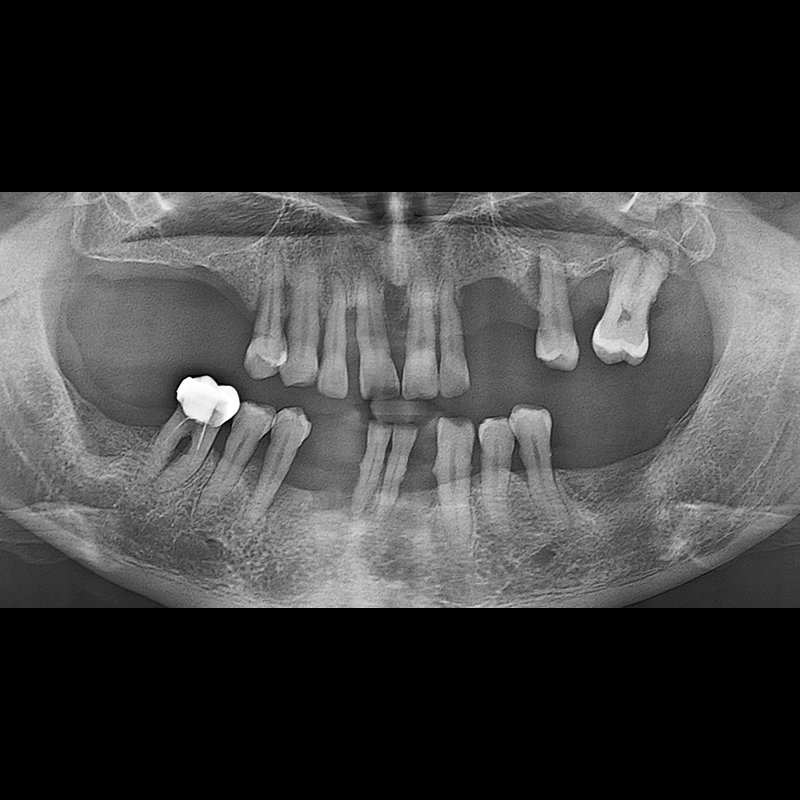

BEFORE AFTER

Implant before and after 2025.05.30

Implants were placed in the missing tooth and in the tooth position where it was difficult to save.